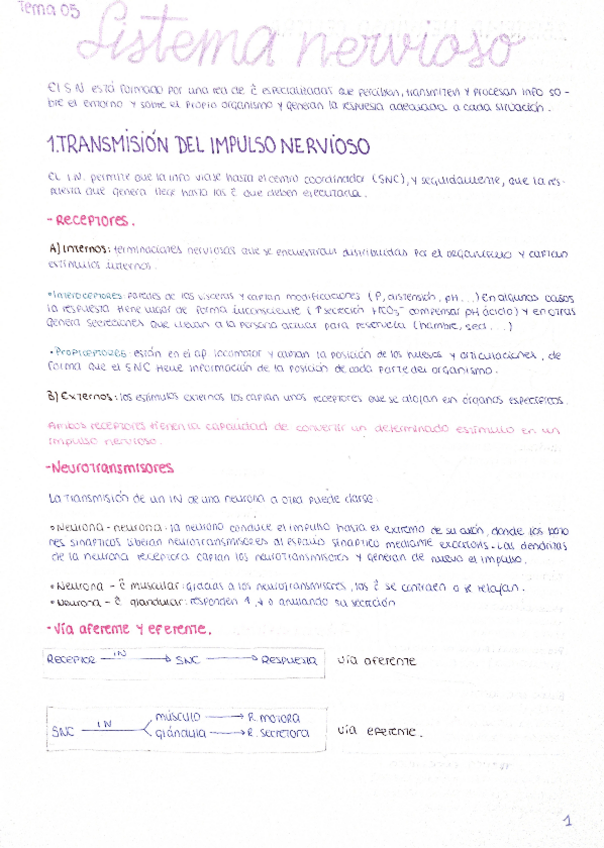

He publicado nuevos apuntes de Fisiopatología general: sistema-nervioso.pdf

He publicado nuevos apuntes de Fisiopatología general: Tema-7-Fsiopatologia-neurologica.pdf